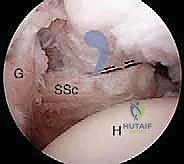

2. إحداث الثقوب (Portals) واستكشاف المفصل

يقوم الدكتور هطيف بعمل 3 إلى 4 ثقوب صغيرة جداً حول الكتف. يُدخل كاميرا المنظار (Arthroscope) لعمل جولة استكشافية شاملة لداخل المفصل، وتقييم الغضاريف، أوتار الكفة المد